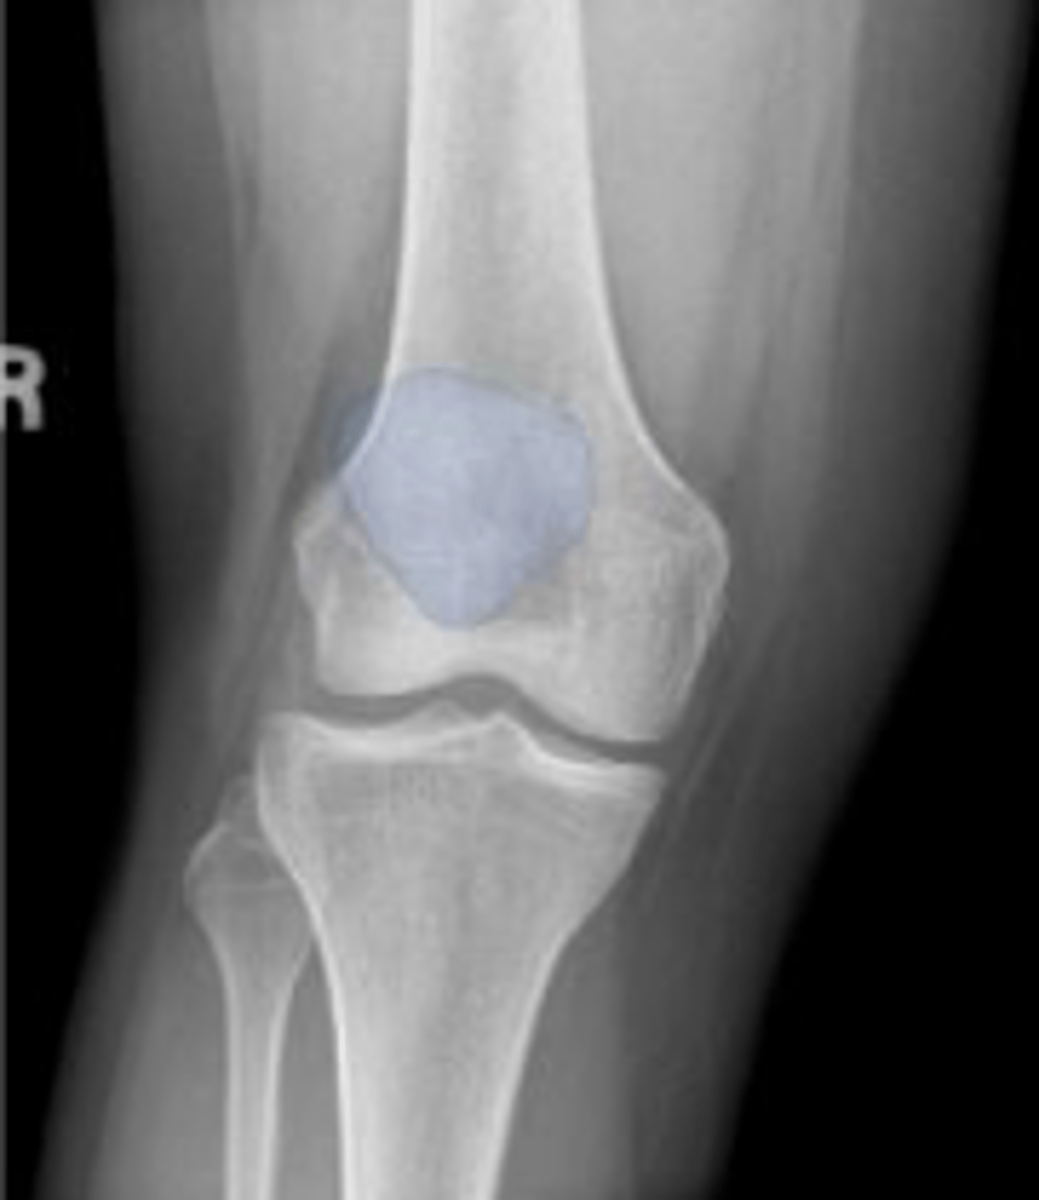

Right AP knee

What is the name of the radiographic view?

Right patella

What is outlined?